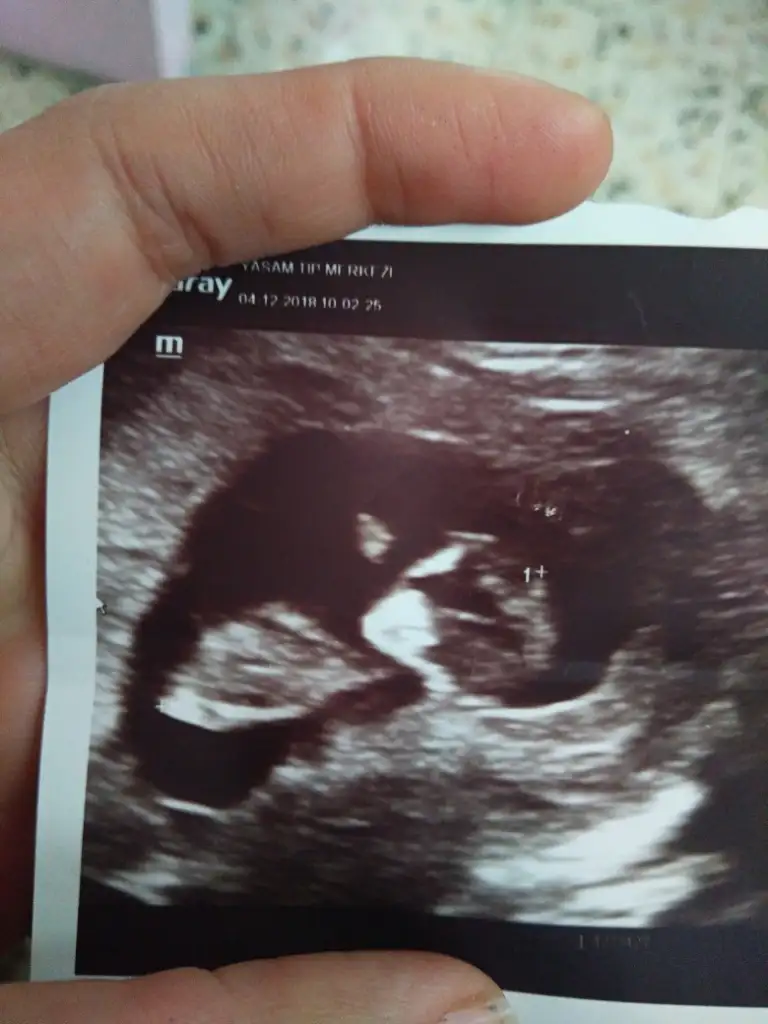

Ay maşallah kuzuya.Erkek gibi geldi bana :)kızlarr napıyorsunuz nasılsınız maalesef sayfa birikmiş okuyamadım hepsini biraz ara buldum iş yerinden foto atayım dedim yorum bekliyorum 10 haftalık ultrason fotosu koyucam kimin içinden ne geçiyo merak ediyorummm

Cnm hic bir fikrm yk masallah diyeyim dedm :)kızlarr napıyorsunuz nasılsınız maalesef sayfa birikmiş okuyamadım hepsini biraz ara buldum iş yerinden foto atayım dedim yorum bekliyorum 10 haftalık ultrason fotosu koyucam kimin içinden ne geçiyo merak ediyorummm